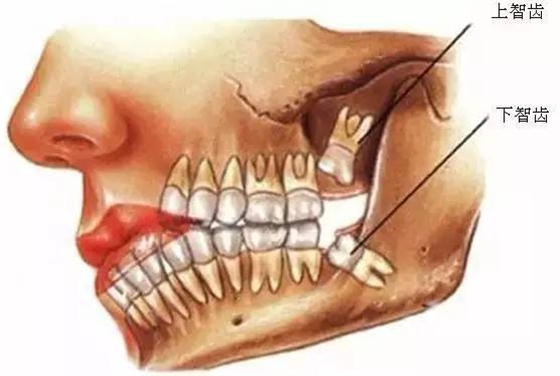

口腔醫(yī)院牙醫(yī)表示,智齒這個磨人的小妖精,簡單的說就是人類演化過程的棄兒。觀察古人類和其他靈長類的頜骨,會很容易發(fā)現(xiàn),他們的頜骨與現(xiàn)代人相比更大,頰舌面寬度更寬,近遠(yuǎn)中向長度更長。頜骨空間充足,智齒的生長方向和咬合關(guān)系一般都比較正常,很少出現(xiàn)現(xiàn)代人智齒阻生的情況,說明頜骨提供的空間跟智齒的萌出狀態(tài)有直接的關(guān)系。

所以,簡單的說智齒實際上是人類演化過程中被放棄的生物學(xué)性狀,由于個體遺傳基因的不同,在這個性狀的表達(dá)上存在差異,是否萌出智齒以及萌出數(shù)量都因人而異,有人是4顆全部萌出,有人只萌出1顆,也有人1顆智齒也不長的。

3、空間缺乏

智齒在人類的演化史上,是歸于消逝狀態(tài)。因而牙弓也越來越小,空間缺乏的狀況是很多見的。以萌生的時分最能感受到腫脹、疼痛感。很多人即是因為不能忍耐這種疼痛感,而決議拔掉智齒。

6、阻生齒

一般這是最討厭的一種,牙醫(yī)會覺得很難搞定,但患者卻不一定有感受,因而忽略了。這一種類型的牙齒,一般埋在齒槽骨的里邊,假如會痛,或是確診會有病灶發(fā)作的時分,就需求拔除了。